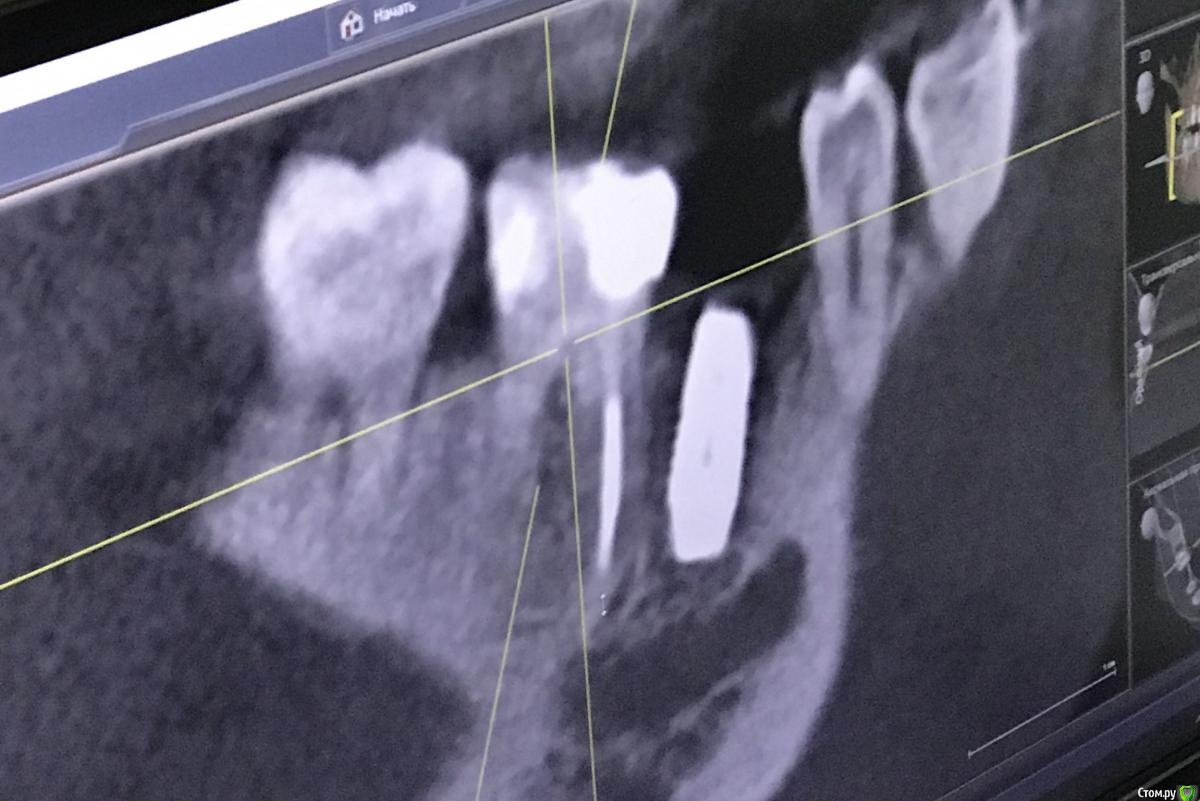

111 Опубликовано 25 декабря, 2020 Поделиться Опубликовано 25 декабря, 2020 Здравствуйте, уважаемые доктора,Посмотрите, пожалуйста, снимки и дайте Ваше видение ситуации.Субъективно - иногда с пульсацией побаливает область между 45 и 46. Но не часто совсем. Сам по себе 46 никаких ощущений не вызывает, был пролечен под микроскопом. Ортопедию не делали из-за наблюдения за 45. Ссылка на комментарий

111 Опубликовано 26 декабря, 2020 Автор Поделиться Опубликовано 26 декабря, 2020 (изменено) Iroil, спасибо большое за ответ.46 был кариес но не болел, периодонтита не было, никаких воспалений на верхушках не было. То есть 46 просто пролечили - обработали каналы, заложили кальций, и тд. Делалось под микроскопом, доктор очень хороший. По поводу 45 - изначально кости было достаточно по высоте, по объему пришлось подсыпать gen-oss 0,5 в момент имплантации, плюс сст с бугра. Вообще всё было хорошо, особо сильно не болело, без отёка зажило. В момент снятия швов - обнаружилась убыль кости в области 46, слегка оголился корень ближайший к 45, но мы как-то это не обсуждали с доктором. Установили Фдм, все ок.И вот пришло время ортопедии - это было летом 2019 - ортопед не захотел работать с имплантом, у которого на снимке оголена шейка. Десны достаточно при этом. Имплант не запротезирован.Спустя пару дней на визите у хирурга - я прошу выкрутить 45, мне отказывают, принято решение либо оставить как есть, либо подсыпать кости немного.Сейчас, декабрь 2020, я хожу с фдм и уже точно понимаю, что надо переустановить 45, но хирург предлагает 2 варианта:- оставить как есть и делать ортопедию (т.к. десна хорошая);- удалить 45 и 46 для создания удобного рабочего поля и имплантация 45, 46.Вот я пытаюсь понять, нельзя ли просто 45 выкрутить? Аккуратно удалить 45 не получится? (Очень не хочется расставаться с 46, сам по себе он не болит при накусывании и постукивании). Изменено 26 декабря, 2020 пользователем 111 Ссылка на комментарий

Irouil Опубликовано 26 декабря, 2020 Поделиться Опубликовано 26 декабря, 2020 Имплант запротезирован? Когда был установлен? Маловероятно, что описываемые жалобы связаны с имплантатом. Скорее причина в зубе - решение о его лечении лучше спросить в терапевтическом разделе, хирурги зубы не лечат. Если имплантат не запротезирован, то мне кажется логичнее его удалить - очень комрромиссно придется протезировать. Если уже есть коронка - нужен рентген с ней. 1 Ссылка на комментарий